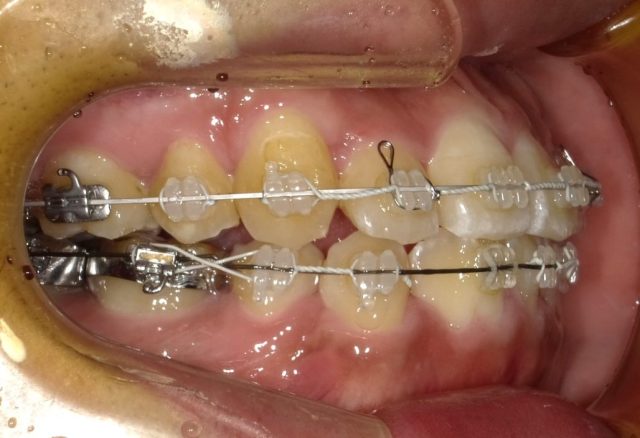

【左側面観】

2023年1月